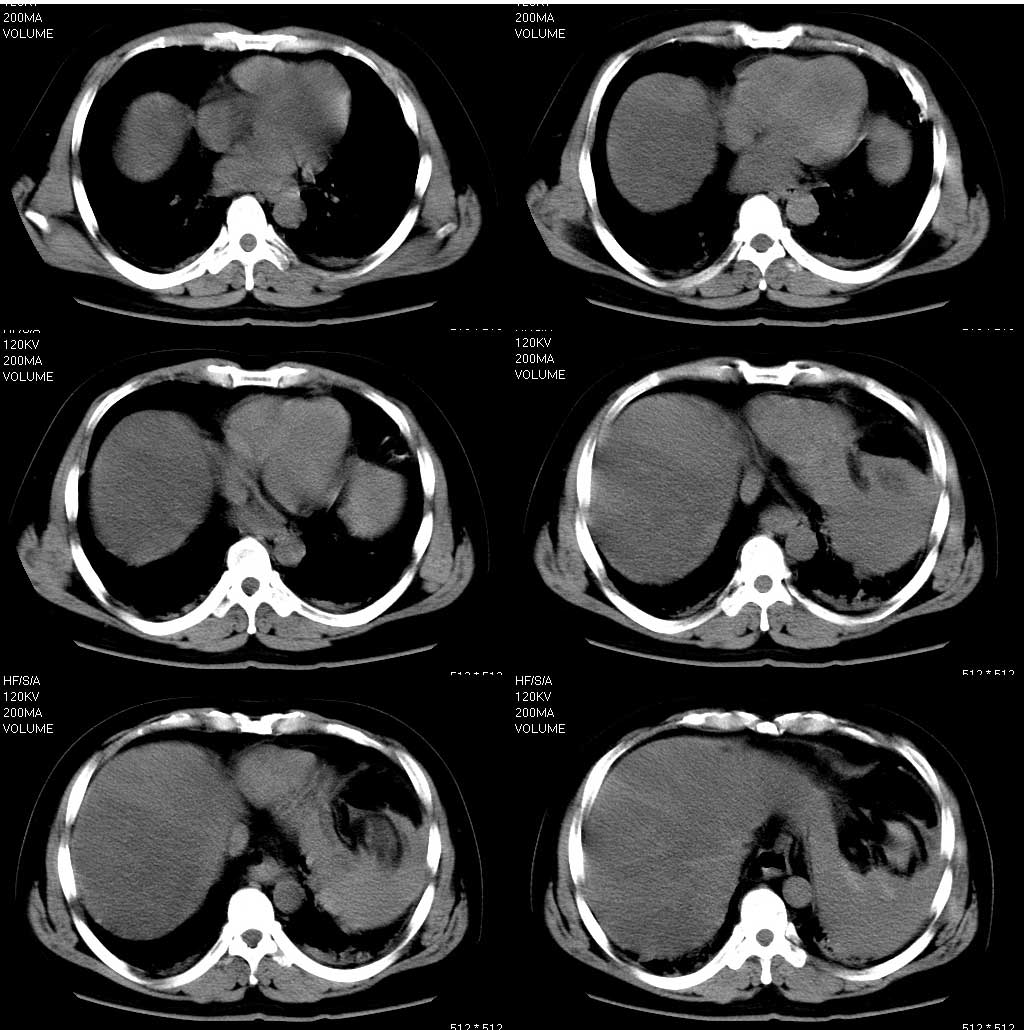

(结果公布:http://www.radida.com/bbs/forum.php?mod=viewthread&tid=56287) 男,47岁。车祸伤及腹部6小时,现腹痛难忍。 诊断性腹穿:(—) 左下胸部穿刺:抽出血性液体。 临床诊断:胸腹部闭合性损伤。 腹 ...

脾脏呈分叶状,脾周及临近腹膜腔多量高密度影(积血),考脾破裂伴腹腔积血,脂肪肝,双侧胸腔积血。